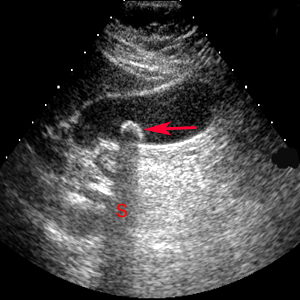

Ultrasound pictures of gall stone

Back to types of ultraspound